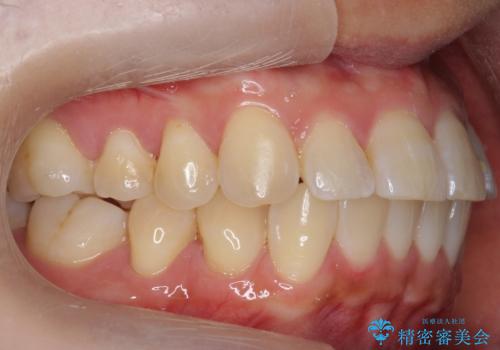

前歯と奥歯の反対咬合 部分ワイヤーとインビザラインで

- 前歯の並びを気にして来院。

左上の前歯が内側に入って反対咬合になっていました。

また、左上5番も反対咬合でした。

上のワイヤー矯正を半年ほど行い反対咬合を改善してから、上下インビザライン治療を行いました。